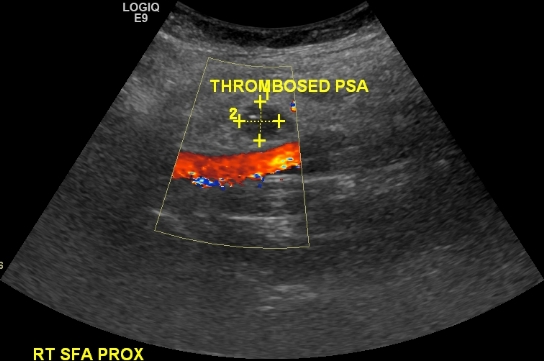

On the day post ablation Ms. X started complaining of groin tenderness. Examination revealed a preserved femoral pulse and a faint bruit that was not noted before. A groin ultrasound was ordered. The main finding is seen in the image below:

This is a pseudoaneurysm. There is a typical to and fro flow pattern in the neck. There is a typical ‘bubble’ with a ‘Yin-Yang’ flow pattern. This pseudoaneurysm measured about 1.2 cm. What would you do in this case?

In this case ultrasound guided compression was chosen. Unfortunately, it did not work. A repeat ultrasound performed on the next day showed the pseudoaneurysm had grown to 1.9 cm. This time thrombin injection was chosen and performed successfully.